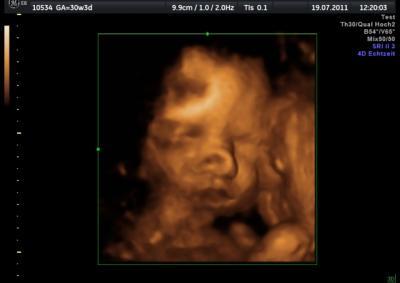

Hallo ihr Lieben, war vorhin beim 3D/4D US und es war sooo schöööön unsere kleine zu sehen Hätte ewig schauen können und sie hat sich von ihrer schönsten Seite gezeigt. So und nun dürft ihr mal gucken, Bild hängt unten dran. VLG Yvi

Bild zu 3D/4D US gehabt:))) - Forum für September - Mamis

Schön, die Nase sieht ja lustig aus! :) Hast du das selbst bezahlen müssen?? LG

Nix ist mit der Nase...ist nur Schatten! Keine Panik machen Mädels, ist alles i.O. mit meiner kleinen. VLG